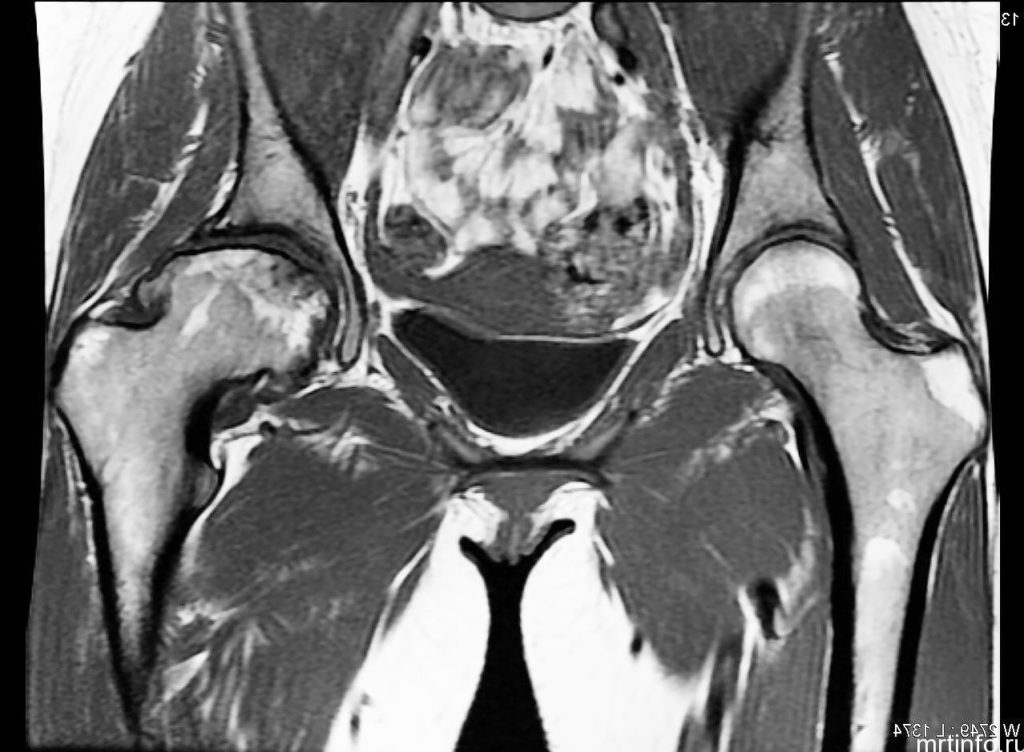

УЗИ, рентген и МРТ тазобедренного сустава обязательно при диагностировании артрозо-артрита

Для постановки диагноза необходимо обратиться к врачу-ревматологу. Необходимые обследования:

- анализ крови,

- рентген тазобедренного сустава,

- УЗИ сустава,

- МРТ или КТ.

Рентген тазобедренного сустава позволяет выявить степень поражения костной и хрящевой ткани, а также точную локализацию и распространение патологического процесса.

УЗИ необходимо для исключения солевых отложений и остеофитов в суставной капсуле или вокруг сочленения костей. МРТ и КТ позволяет визуализировать степень повреждения хрящевой ткани.